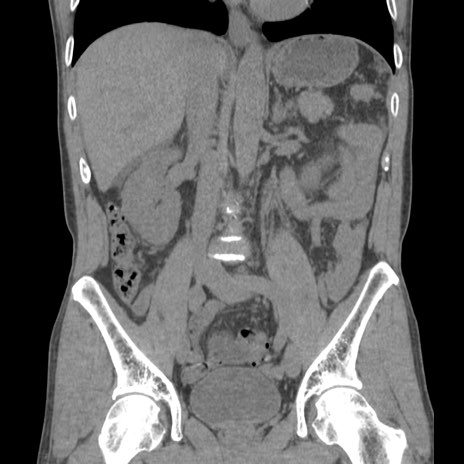

症例56 CT(冠状断像)

横断像